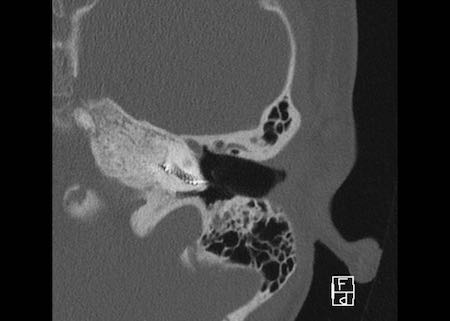

Bên trái là hình ảnh của một bé gái 2 tuổi.

Các hình ảnh từ kết quả chụp CT được thực hiện trước khi cấy ốc tai điện tử.

Quan sát thấy dị dạng nhẹ ở đỉnh ốc tai – không có sự phân tách giữa vòng thứ hai và vòng thứ ba, và trụ ốc tai xương vắng mặt.

Cống tiền đình bình thường.